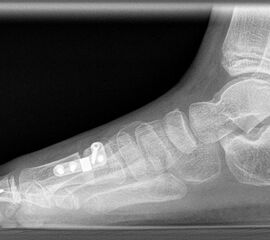

Röntgen

Standard ist die belastete Röntgenaufnahme des Fußes dorso-plantar und seitlich. Günstig ist eine Röhrenkippung von 10°-20°, um die Gelenke der Lisfranc-Linie einsehen zu können.